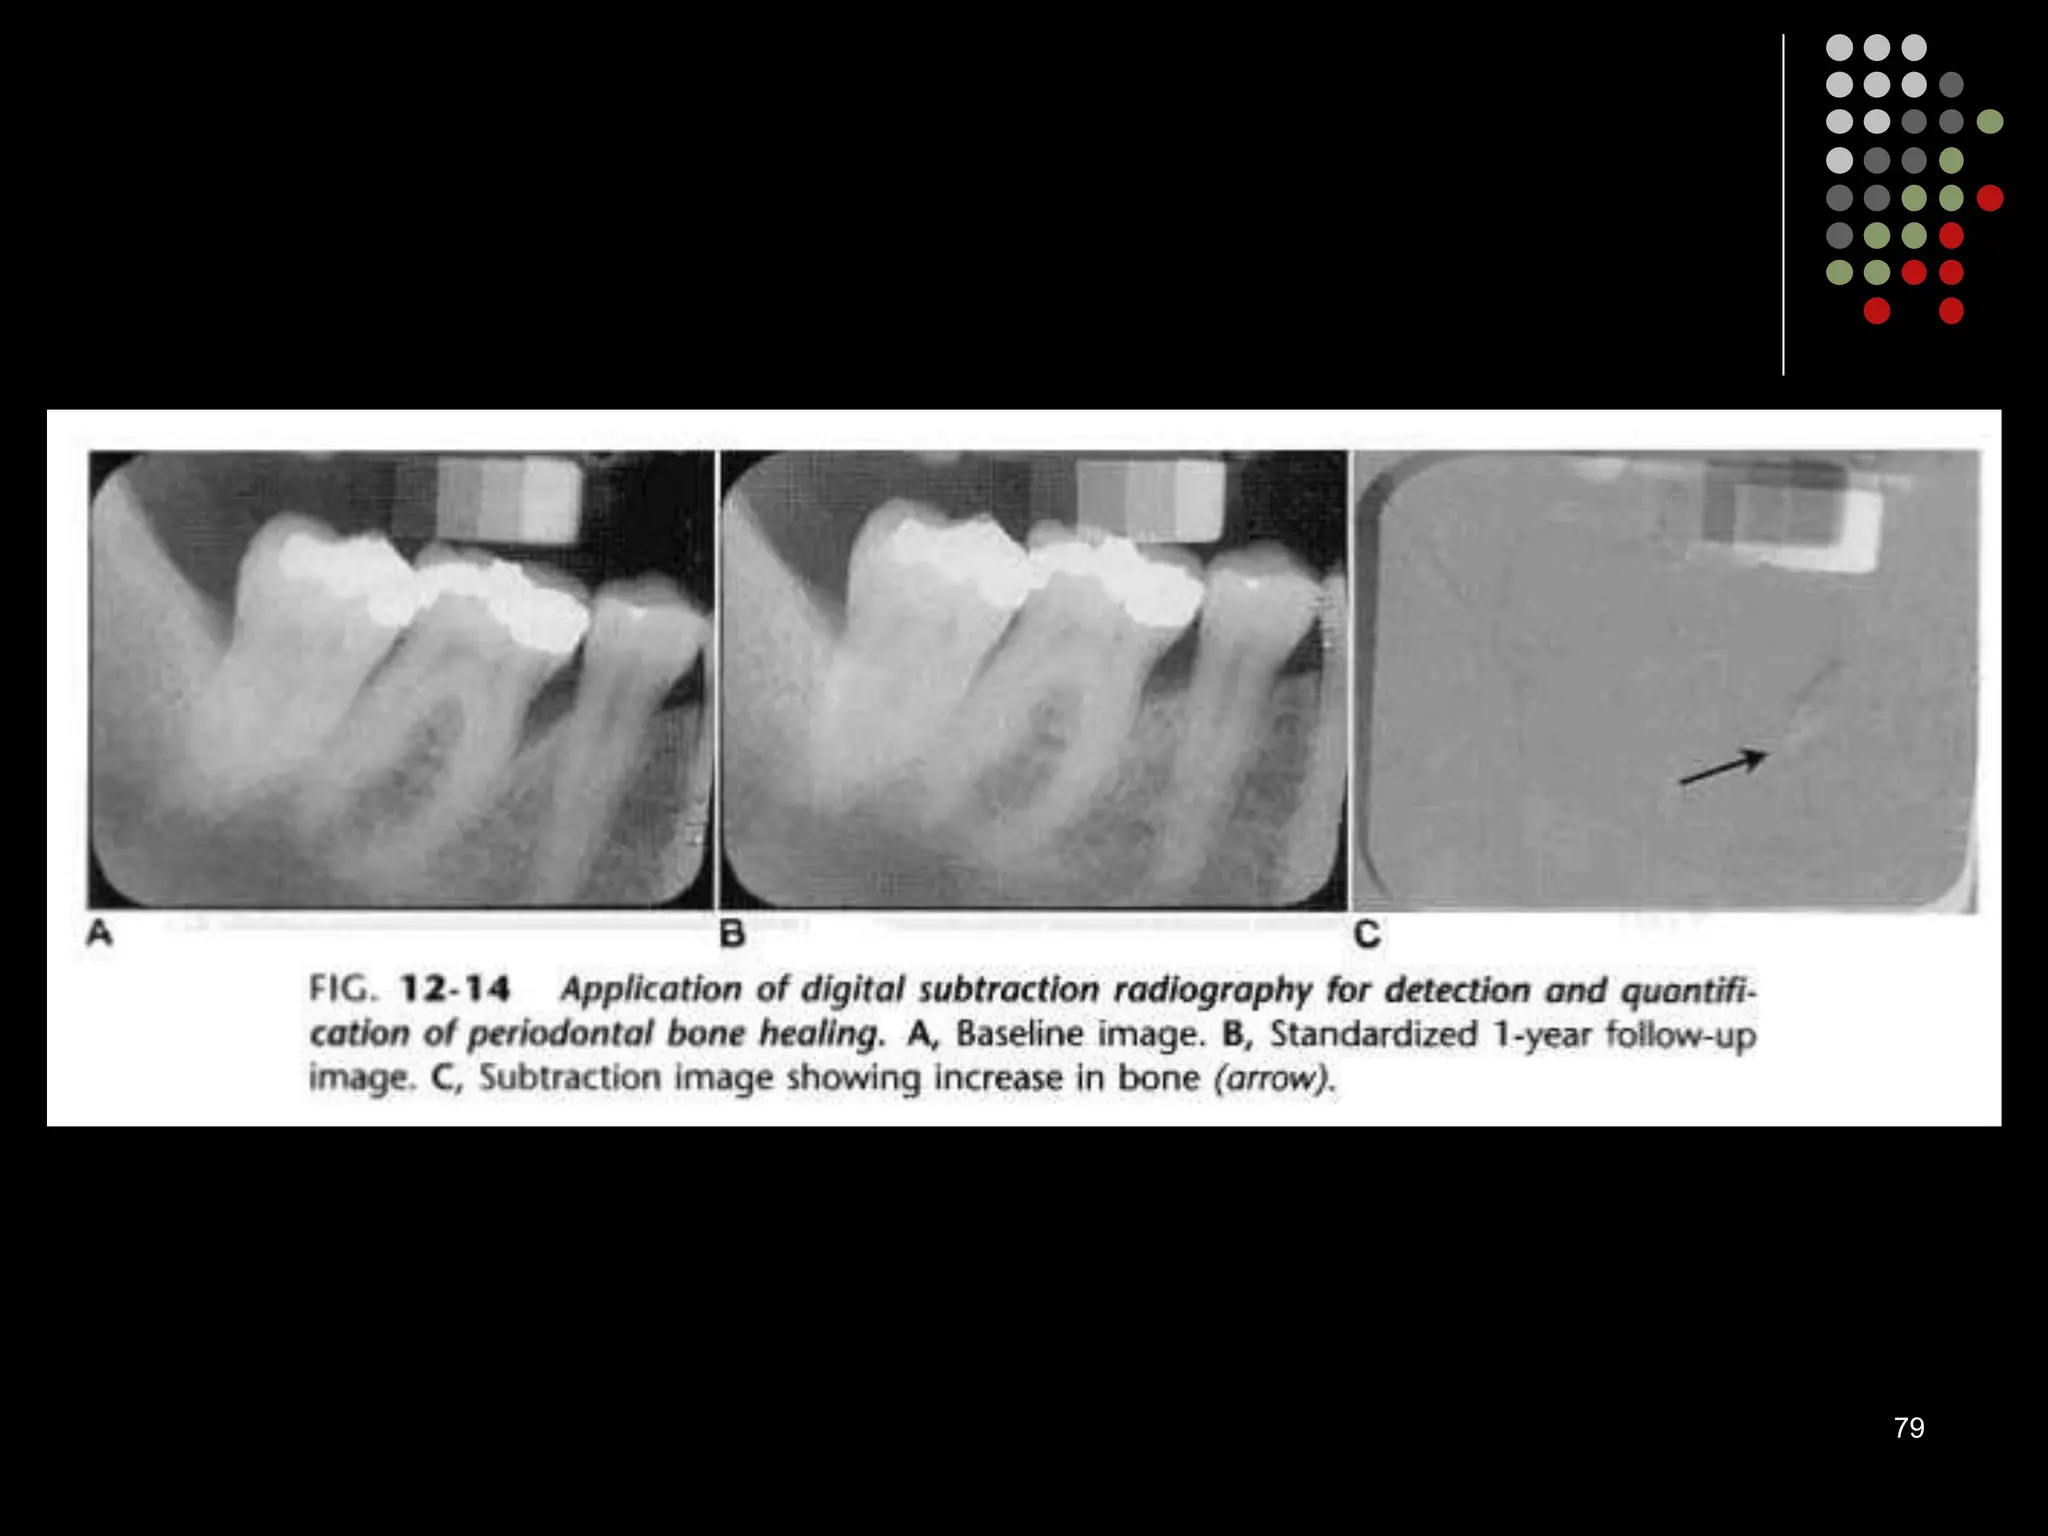

Digital subtraction radiography

 Subtraction in digital radiology is another image enhancement method with purpose

to produce two radiographs of the same area in the mouth at the different time

intervals.

 The first image can be subtracted from the second one to identify changes that may

have occurred during a certain time period. Minimal changes in loss or gain of hard

tissue can be detected using this technique, otherwise undetectable by visual

examination and traditional radiography.

79

80